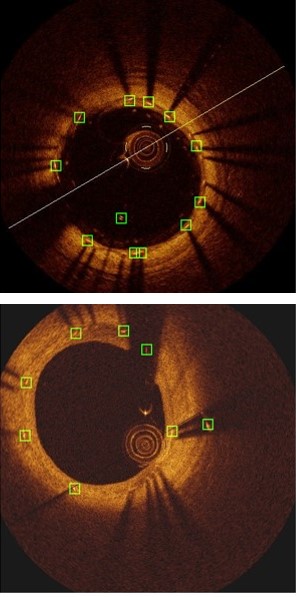

Refer to caption

Figure 3: Strut detection results: (a) Comparison of our method to the existing methods, (b) component analysis of our method.

Table 1 and Fig. 3(b) show the detection results of our method at individual stages. Fig. 5(a) shows the two example detection results with various thickness coverage. The Local-Network shows the higher recall while Global-Network achieved better precision results (as shown in Fig. 5(c) and Fig. 5(d)). As exemplified in Fig. 5(e), the proposed method integrated both Local Network and Global-Network and achieved a better consistent performance in recall and precision.

Table 1, Fig. 3(b) and Fig. 5 compared the main components of our method individually to quantify their contributions to the final detection results. These results demonstrate that Local-Network has higher recall and we attribute this to the usage of patch-based network to detect all the potential strut candidates. In contrast, Global-Network achieved higher precision for its ability by adding global context, e.g., appearance information, as part of the learning process, which ensures all the detected struts are consistent with the shape of the stent. Table 1, Fig. 3(b) and Fig. 5 also show the advantages from our combination which integrates complementary detection results produced at individual components.